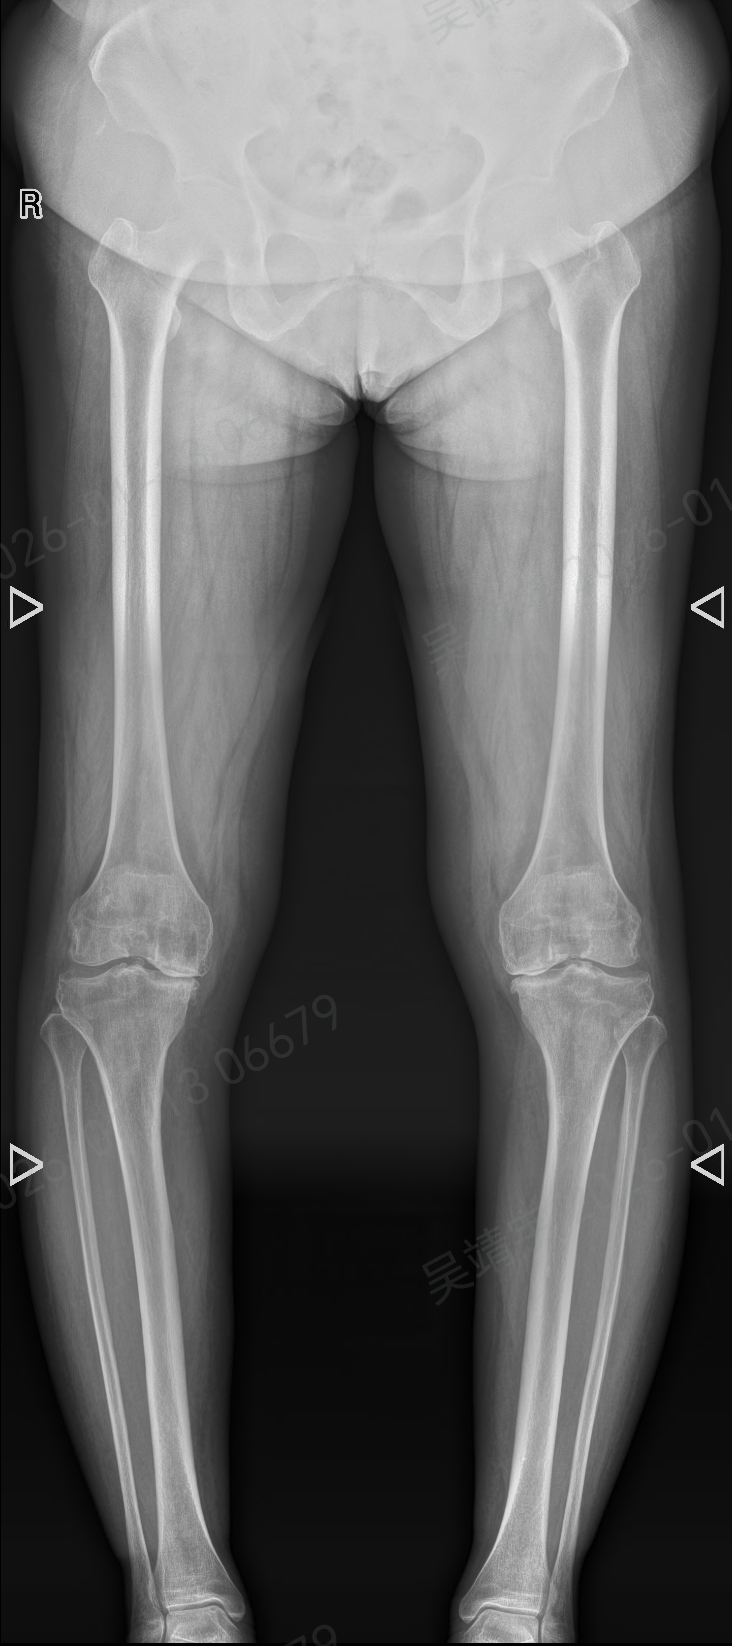

患者张阿姨(化名)的膝关节受骨关节炎影响已达10年,期间出现软骨严重磨损、骨质增生、关节畸形等问题,日常行走功能严重受限,每一步都伴随明显疼痛,尝试药物、理疗等多种方式后,改善效果不佳。

对于这类病程长、关节病变复杂的病例,传统全膝关节置换术需依赖医生临床经验完成骨骼切割、假体安放等关键操作,而关节力线校准、假体角度把控等环节对精度要求极高,操作偏差可能影响术后关节功能恢复,诊疗难度较大。